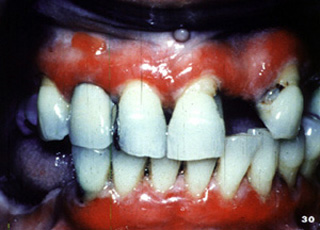

También pueden afectarse otras áreas del mucosa oral. Este señor presenta ulceraciones dolorosas de los mucosa bucal y labio. El examen clínico reveló  úlceras superficiales irregularmente formadas.

En otra vista, las lesiones están presentes en la mucosa yugal y la encía edentula.